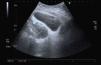

Pruebas complementarias: leucocitos: 19.500/μL (86% neutrófilos), proteína C reactiva: 36,2 mg/dl; análisis de orina: proteinuria 30 mg/dl, esterasa leucocitaria 500 células/μl, 5-10 hematíes/campo, piuria y bacteriuria; urocultivo > 100.000 UFC de Escherichia coli; prueba de embarazo, negativa. Ecografía abdominal: imagen ovalada y avascular de 8 × 8 × 12 cm en fondo de saco de Douglas (fig. 1). En el tacto rectal se palpaba como una masa fluctuante y dolorosa ventral al recto.